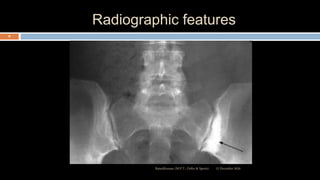

Radiographic features

 Sacroiliac joint –

 Erosion & sclerosis of bone near the articular

surface

 Ankylos later

 Spine –

 Apophyseal joint erosion

 Squaring of the vertebral bodies with ossification of

disc margins

 Syndesmophytes

 “Bamboo Spine” due to calcification of longitudinal12 December 2020Ratankhuman (M.P.T., Ortho & Sports)

Radiology

 The radiograph of pelvis show signs of sacroiliitis

 Severity of sacroiliitis can be graded from 0 to IV of the SI

joints.

 At early stages, sacroiliitis can be detected with CT &

MRI before the abnormalities at plain radiograph of pelvis

.